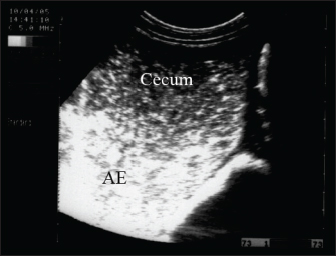

Sand colic

Swallowing sand can cause acute or recurrent fits of colic and/or diarrhea, poor performance, and weight loss (Korolainen and Ruohoniemi, 2002). Owing to the non-specificity of such changes, diagnosis based solely on clinical symptoms is difficult. To assist in sand detection, per rectum palpation of sand-filled organs, abdominal auscultation, sonography and radiography, and fecal sand sedimentation tests can be implemented (Keppie et al., 2008). Mild-to-severe fits of recurrent colic are associated with abdominal distension (80%), diarrhea (20%), and loss of appetite (10%). Signs of intense or persistent colicky pain are associated with an increased possibility of colon displacement or volvulus. The diarrhea is usually watery but not malodorous or profuse, and the affected animal is sometimes mildly pyrexic and frequently tachycardic (Kendall et al., 2008). Abdominal auscultation over the cranial ventral region revealed sounds that appeared to be heard when a paper bag was partially filled with sand and rotated (Kilcoyne et al., 2017).

Radiography will detect sand in the dorsal and ventral colons and can be used to predict the efficacy of therapy. The intensity of sand accumulation can be estimated by radiography and grade assignment. However, abdominal sonography has good specificity and sensitivity (88%) versus the gold standard of radiography in the detection of sand in the ventral colon (Fig. 11). Conversely, ultrasound is not valuable in detecting sand in the transverse or right dorsal colon (Kendall et al., 2008). Management includes the re-establishment of electrolyte and fluid abnormalities, the administration of pain killers, the prevention of sand infection, and at the same time removal of the sand from the surroundings (Kaikkonen et al., 2016). In equids with severe colicky pain, surgical removal is indicated in cases with acute transverse or right dorsal obstruction by sand, displacement, or volvulus. Animals that require surgical intervention for sandy colic with other gastrointestinal disorders have a worse prognosis than those requiring only medical therapy (Hart et al., 2013). Oral magnesium sulfate (1 g/Kg) or mineral oil (1 ml/kg) can accelerate the removal of sand (Niinisto et al., 2018).

Fig. 11. Ultrasonography of a female donkey exhibiting sand colic. Case history included a recurrent episode of severe abdominal pain. Rectal examination revealed a large amount of sand in the feces. Abdominal ultrasonography shows cecal impaction with sand. Acoustic enhancement (AE) within the cecum was a characteristic sonographic finding.